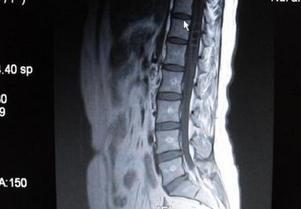

脊髓空洞癥就是脊髓的一種慢性、進(jìn)行性的病變。病因不十分清楚,其病變特點(diǎn)是脊髓內(nèi)形成管狀空腔以及膠質(zhì)增生。常好發(fā)于頸部脊髓。當(dāng)病變累及延髓時(shí),則稱為延髓空洞癥。

脊髓空洞癥多數(shù)情況下是由于先天性發(fā)育異常,或者是由于后天因素所導(dǎo)致出現(xiàn)的, 多數(shù)見于合并有小腦扁桃體下疝,或者是其他緩解畸形等疾病。

脊髓空洞可能會(huì)引起病變平面以下軀體感覺異常、肢體無力、運(yùn)動(dòng)障礙、大小便異常,甚至出現(xiàn)截癱等癥狀表現(xiàn)。